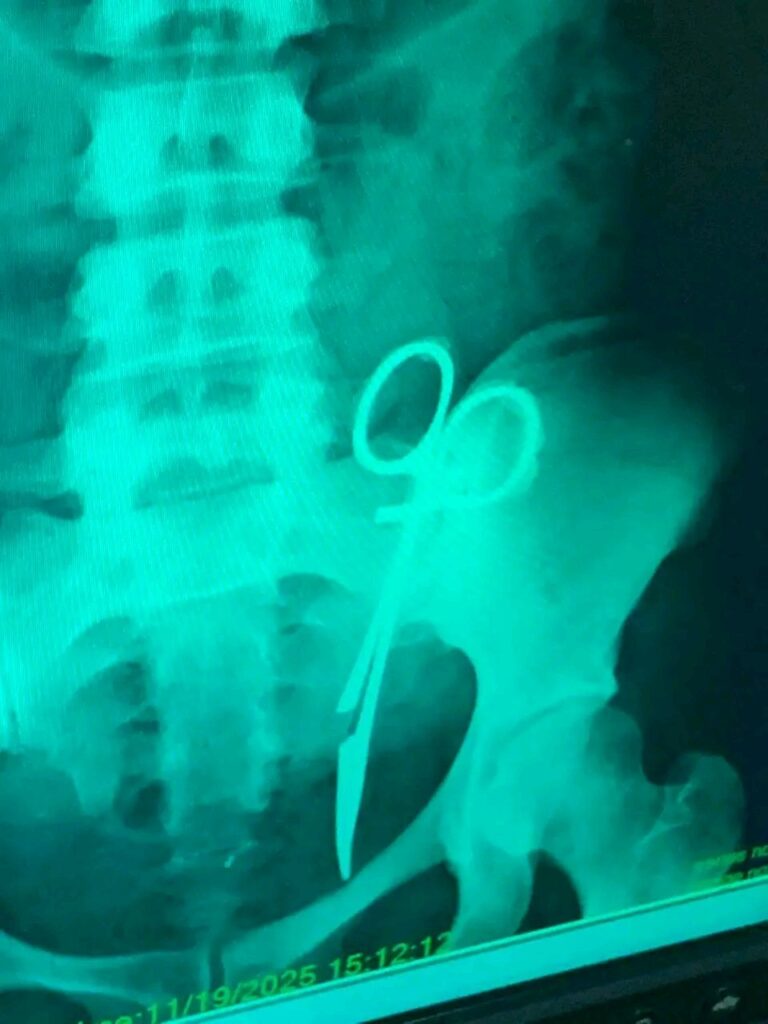

The story was she had gone in for a cesarean section in 2013 and a doctor forgot a scissors inside her tummy.

The doctor inquired if she had tried an X-ray, and she said no. They immediately carry out an X-ray and “behold my people see wetin dey inside my friend body for 12 years ” , the friend said, sharing a photo of the result: